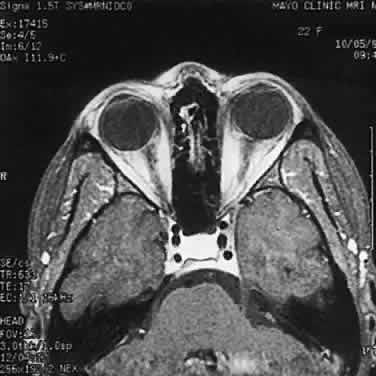

Computed tomographic (CT) and magnetic resonance imaging (MRI) have had a significant impact on the management of patients.29 Many tumors are diagnosed based on imaging features alone, without tissue confirmation (Fig. 35). They typically show a demarcated fusiform enlargement of the nerve, which may be kinked and indent the globe. On T2-weighted MRI, a circumferential component surrounds a compact core of low signal intensity.23 MRI is particularly useful in assessing the extent of the lesion.

Fig. 35. Computed tomographic scan showing left optic nerve glioma.